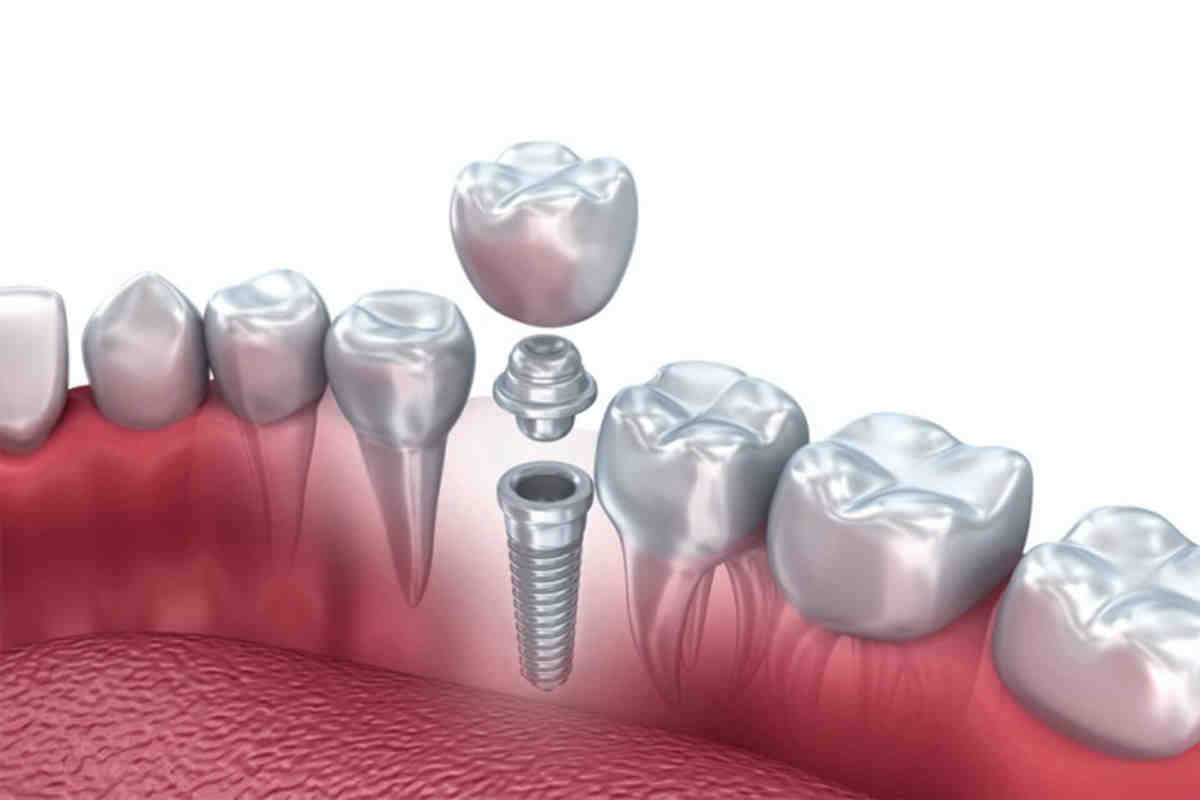

Why are implants so expensive?

If you’ve been wondering why dental implants cost so much, the reasons are: Dental implantation is a complex and cosmetic process. Pay for the skills of the dentist. Implant posts and dental crowns add to the cost.

Are teeth implants painful?

Dental implants are considered the best options to replace missing or damaged teeth. The procedure itself is not painful as it is performed under general or local anesthesia to completely numb the mouth. After dental implantation, once the numbness subsides, the patient may notice mild pain.